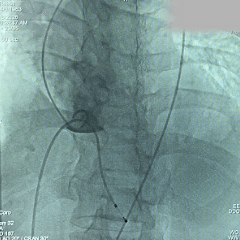

术中影像

根部造影:可见大量反流

导丝跨瓣

预弯型系统顺利跨过横位心

平齐窦底猪尾,0位定位

展开后造影,瓣膜位置偏深

回收后再次释放